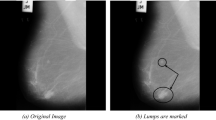

Breast cancer is one of the leading causes of mortality in the world and it occurs in high frequency among women that carries away many lives. To detect cancer, extraction or segmentation of lesions/tumors is required. Segmentation process is very crucial if the mammogram images are blurred or low contrast. This paper suggests a novel clustering approach for segmenting lesions/tumors in the mammogram images using Atanassov’s intuitionistic fuzzy set theory. The algorithm initially converts an image to an intuitionistic fuzzy image using a novel intuitionistic fuzzy generator. From the intuitionistic fuzzy image, two membership intervals are computed. Then, using Zadeh’s min t-conorm, a new membership function is computed. Using the new membership function, an interval type 2 fuzzy image is constructed. Two types of distance functions are used in clustering—intuitionistic fuzzy divergence and a fuzzy exponential type distance function. Further, in each iteration, membership matrix is updated using a hesitation degree and a clustered image is obtained. Tumors/lesions are then segmented from the clustered image. The proposed method is compared with existing methods both quantitatively and qualitatively and it is observed that the proposed method performs better than the existing methods.

Chaira, T. An Intuitionistic Fuzzy Clustering Approach for Detection of Abnormal Regions in Mammogram Images. J Digit Imaging 34, 428–439 (2021). https://doi.org/10.1007/s10278-021-00444-3